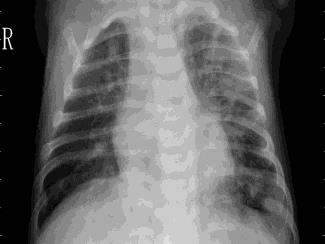

Pneumonia, a respiratory infection brought on by bacteria or viruses, affects a large number of people, especially in developing and impoverished countries where high levels of pollution, unclean living conditions, and overcrowding are frequently observed, along with insufficient medical infrastructure. Pleural effusion, a condition in which fluids fill the lung and complicate breathing, is brought on by pneumonia. Early detection of pneumonia is essential for ensuring curative care and boosting survival rates. The approach most usually used to diagnose pneumonia is chest X-ray imaging. The purpose of this work is to develop a method for the automatic diagnosis of bacterial and viral pneumonia in digital x-ray pictures. This article first presents the authors' technique, and then gives a comprehensive report on recent developments in the field of reliable diagnosis of pneumonia. In this study, here tuned a state-of-the-art deep convolutional neural network to classify plant diseases based on images and tested its performance. Deep learning architecture is compared empirically. VGG19, ResNet with 152v2, Resnext101, Seresnet152, Mobilenettv2, and DenseNet with 201 layers are among the architectures tested. Experiment data consists of two groups, sick and healthy X-ray pictures. To take appropriate action against plant diseases as soon as possible, rapid disease identification models are preferred. DenseNet201 has shown no overfitting or performance degradation in our experiments, and its accuracy tends to increase as the number of epochs increases. Further, DenseNet201 achieves state-of-the-art performance with a significantly a smaller number of parameters and within a reasonable computing time. This architecture outperforms the competition in terms of testing accuracy, scoring 95%. Each architecture was trained using Keras, using Theano as the backend.